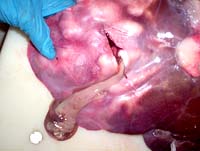

-Sau 5 ngày, bệnh nhân xuất hiện chảy máu tiêu hóa trên, kiểm tra cấp cứu nội soi cho thấy chảy máu từ OMC. Thực hiện lại ERCP, cho thấy một vùng xa của OMC bị lấp đầy bởi dị vật, không đồng nhất, đường mật dãn nhẹ. Sau khi bóc lấy cục nghẽn, một luồn máu phun raà quyết định chuyển sang mổ bụng cấp cứu;

-Thăm dò toàn bộ OMC trong khi mổ cho thấy một vết loét ở phần giữa của OMC và chảy máu động mạch tại đây với số lượng và thấy một sán chết ngay tại chỗ loét, nhóm phẩu thuật cũng cho biết không điểm chảy máu này không liên quan đến thủ thuật cắt cơ vòng trước đây. Tiến hành mở thông OMC, bằng cách cắt OMC bán phần, mở thông gan-hỗng tràng và cắt bỏ túi mật. Tiếp tục điều trị thuốc kháng sinh và triclabendazole liều 10mg/kg cân nặng (một loại biệt dược mới của Triclabendazole) Sau đó bệnh nhân nằm viện 24 ngày chăm sóc vết mổ và kiểm tra sau phẩu thuật, nay hoàn toàn bình phục.